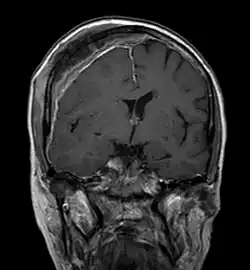

Magnetresonanztomografie

Mit der Magnetresonanztomografie (MRT) können insbesondere Weichteilgewebe gut bildmäßig dargestellt werden. Sie gilt für die Diagnostik von spinalen Metastasen (Metastasen in der Wirbelsäule) als Goldstandard. Mit der MRT können darüber hinaus weitere Komplikationen im Bereich der spinalen Metastasen, wie beispielsweise Infektionen oder Verletzungen des Bandscheiben- und Ligamentkomplexes, Knochenmarködeme nach einer frischen Fraktur,[117][118] oder Kompressionen neuraler Strukturen, sichtbar gemacht werden.[18]:16 Mit Hilfe der STIR-Sequenz (engl. short tau inversion recovery) ist es möglich, das Alter einer Fraktur zu ermitteln. Zum Aufspüren von Metastasen ist die T1-Wichtung mit Gadolinium-haltigen Kontrastmitteln, wie beispielsweise Gadotersäure, besonders gut geeignet. Das Kontrastmittel reichert sich in den Metastasen besonders stark an.[18][119]

Für die Rezidivdiagnostik ist die MRT besser als die CT geeignet. So erzeugen Titanimplantate bei der MRT weniger Artefakte.[85][120]